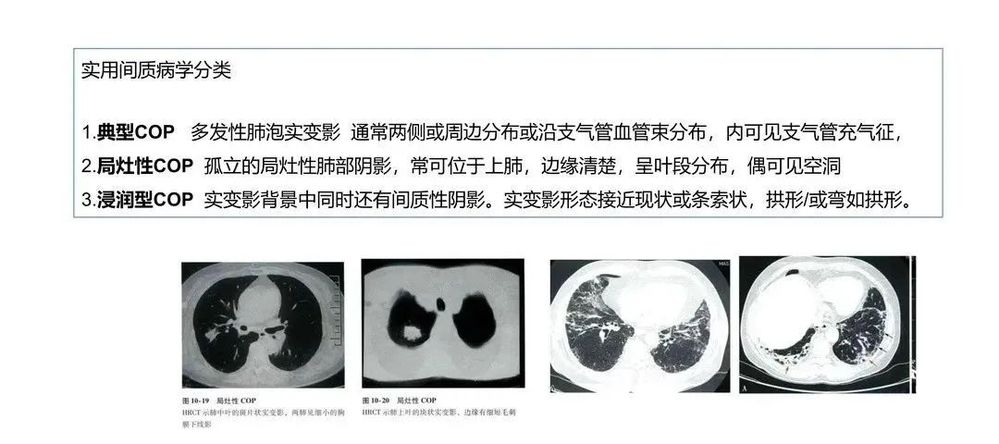

COP肺部CT表现多数为肺泡实变影,可从2cm至双侧广泛病变,病灶多位于胸膜下或肺野外带。病灶呈不规则斑片状,累及多个肺段。部分患者同时可见网状影、不规则线状影和结节影。网格状阴影较少见,很少有胸腔积液等胸膜渗出征象。

①多态性:可呈斑片状、肺实变状、团块状、条索状、地图状、结节状、粟粒状、网织状、蜂窝状等各种形态,以前四种比例较高。每例患者多同时具有两种以上的形态。

通常情况下,提示COP诊断的第一线索来源于其影像学的特点,经过抗感染等治疗效果不佳,结合病理改变,排除其他疾患后诊断为COP。

局灶性机化性肺炎

局灶性机化性肺炎相对少见(见于<15%的COP患者),患者常无症状。单发病灶通常可通过 手术切除治愈。局灶性机化性肺炎必须与肺癌鉴别。